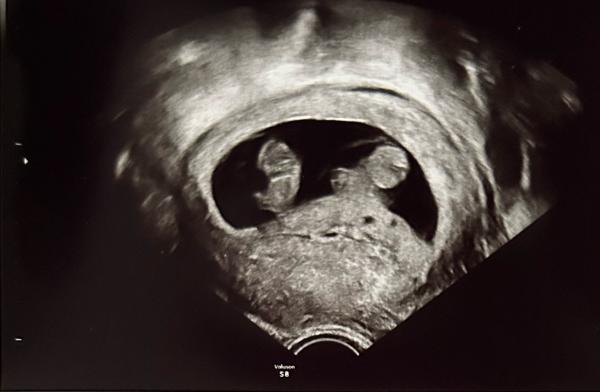

Hallöchen!  Bin recht frisch hier und habe am Montag erfahren, dass wir Zwillinge erwarten 😅🥳 Es ist meine erste SSW und das hat meinen Mann und mich doch ganz schön von den Socken gehauen!  Auf dem Ultraschallbild sieht man ganz leicht die beiden Fruchthöhlen, die FA meinte es wären zweieiige.  Nun habe ich viel gelesen und recherchiert und bin über diese vielen Zwillings-Kombinationen gestolpert 🫣  Nun frage ich mich, ob die beiden doch auch eineiig sein können, sich also jeder in seiner Fruchthöhle befindet und sie sich aber die Plazenta teilen? Und wenn ja, ob die FA das direkt beim US gesehen hätte?  In meinem Mutterpass ist "Monoamniotisch" nicht angekreuzt. Ich bin aktuell 10+1, den nächsten Termin zum Schallen habe ich erst in knapp drei Wochen. Dort wird dann auch der HarmonyTest gemacht.  Sieht man bis dahin dann die Plazenta bzw. zwei? Sodass man auf MoDi oder DiDi schließen kann? Und ist ein Besuch bei der Pränataldiagnostik bei Zwillingen generell notwendig und sinnvoll?   Fragen über Fragen 🙂🥲 Danke schon jetzt für eure Einschätzung oder einfach liebe Worte 🥰🫶🏻

Bild zu Zwillinge - DiMo oder DiDi? - Mehrlinge - für Eltern mit Zwillingen, Drillingen und mehr